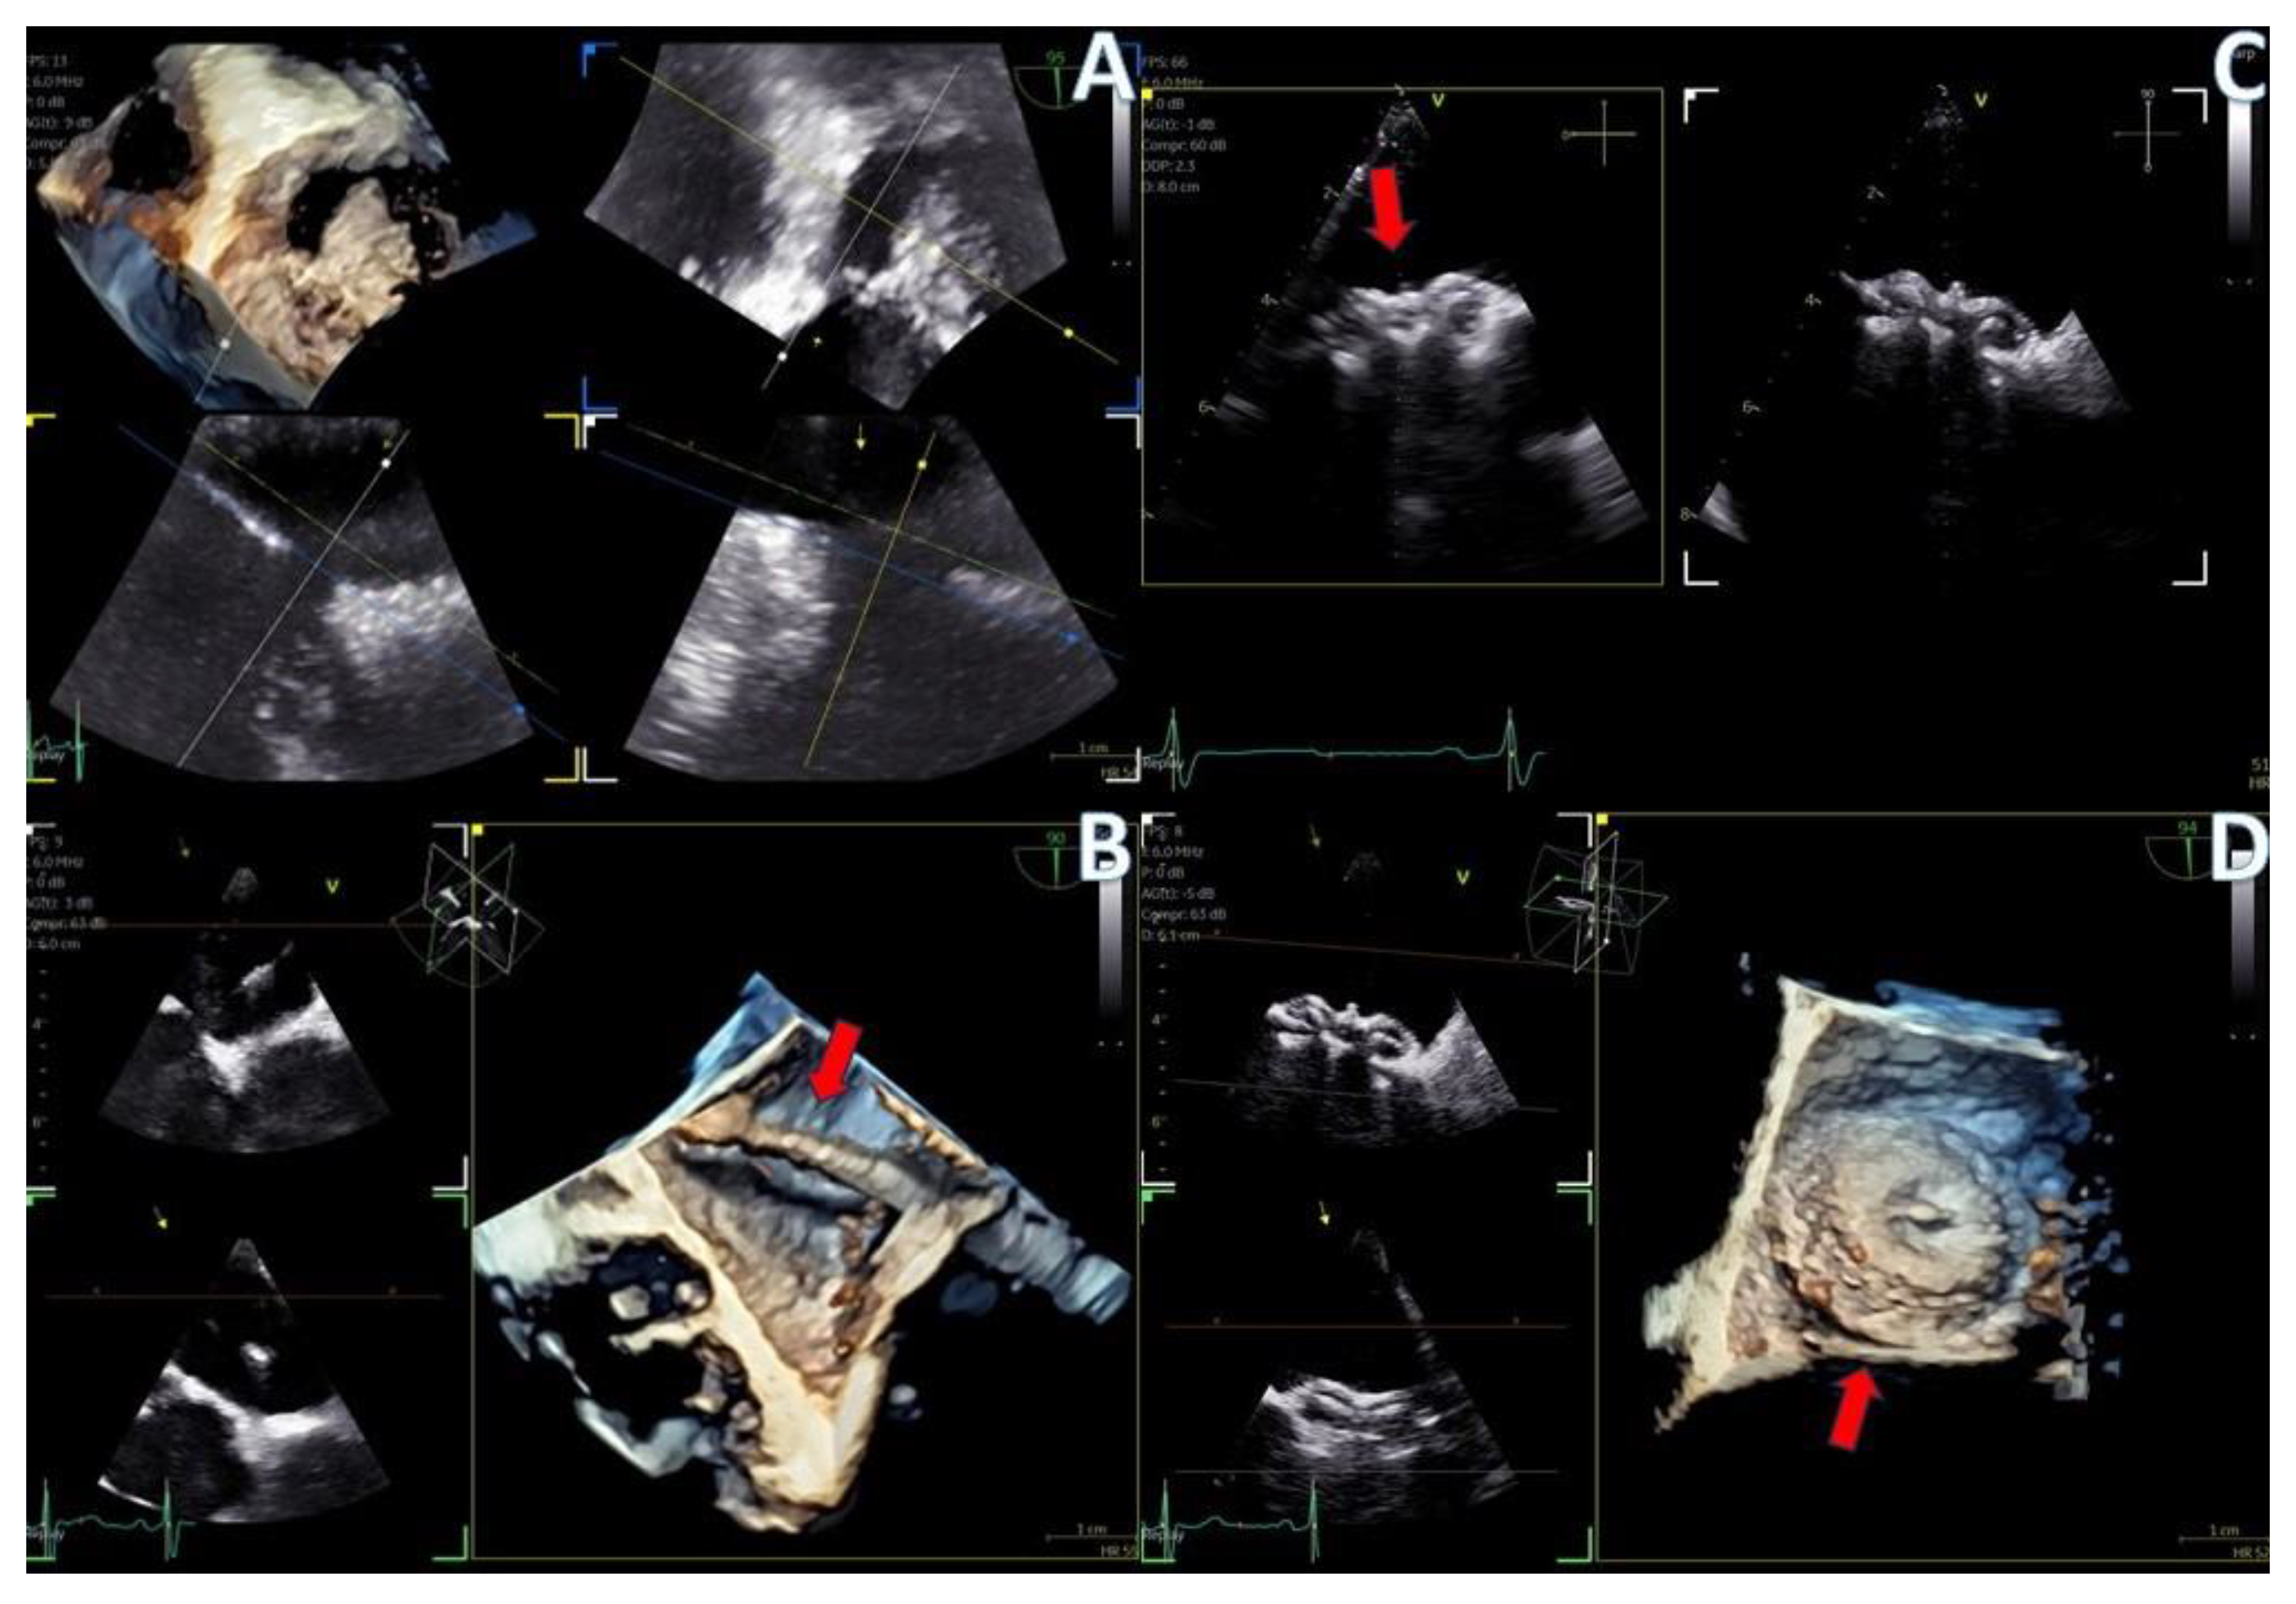

The adult probe was initially inserted for complete 2D/4D image acquisition, followed by the insertion of the pediatric probe while the patient remained under sedation. Remarkably, insertion of the pediatric probe was effortless in all cases, requiring no additional sedation. Despite encountering challenging diagnostic scenarios in all three cases (1st patient: combined severe aortic stenosis and severe mitral regurgitation (MR) due to P1 scallop prolapse, 2nd patient: malfunction of metallic mitral valve prosthesis with an occluded disk, 3rd patient: bioprosthetic aortic valve with paravalvular leak and significant MR in previously MV repair with a complete ring), the pediatric probe consistently provided high-quality images comparable to those obtained with the standard adult probe (Figure 1 and Figure 2, video S4). Notably, there was no compromise in 2D and 4D spatial and temporal resolution, with only minor differences observed compared to the adult 6VT-D probe (Table 1). Evaluation using the 5-point scoring system consistently yielded an average score close to 5 for all three cases, indicating excellent image quality (Table 1).

Figure 1.

Direct comparison of 3D volume −rendered “en face” images of a metallic prosthetic mitral valve with occluded disk. Left image corresponds to 6VT−D adult probe and right image corresponds to 9VT−D pediatric probe.

Figure 2.

Direct comparison of 3D volume-rendered “en face” images of a metallic prosthetic mitral valve with occluded disk. Left image corresponds to 6VT−D adult probe and right image corresponds to 9VT−D pediatric probe. Images enhanced with “photorealistic method” with Flexilight application (GE Healthcare).